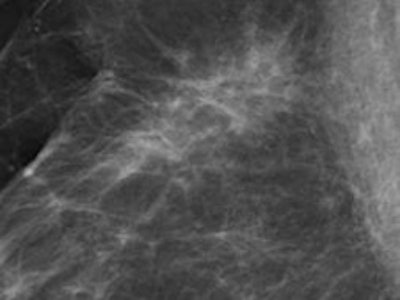

The value of annual mammography screening remains controversial, but for the most part radiologists agree on its utility. With the development of full-field digital mammography, even more cancers are detected, especially in women with dense breasts. The major drawback, however, is "the difficulty of finding and discerning a subtle change against the complex background of the glandular tissue, a particular issue for younger premenopausal women with a so-called dense glandular background pattern," wrote Dr. Matthew Wallis, a consultant radiologist and the director of the Cambridge and Huntingdon Breast Screening Service in the U.K. (Radiol, 24 January 2012, online first).

With tomosynthesis, low-dose images are obtained over a limited arc, and the projections are mathematically reconstructed into a series of sections with the hope that specificity and sensitivity will be improved. Initial work using tomosynthesis as an add-on to conventional 2D mammography suggested the potential for substantial improvements in specificity, the authors noted. They compared the diagnostic accuracy of 2D digital mammography with that of two-view (mediolateral and craniocaudal) and single-view (mediolateral oblique) tomosynthesis in an observer study involving two institutions: Cambridge and Capio St Göran's Hospital in Stockholm.